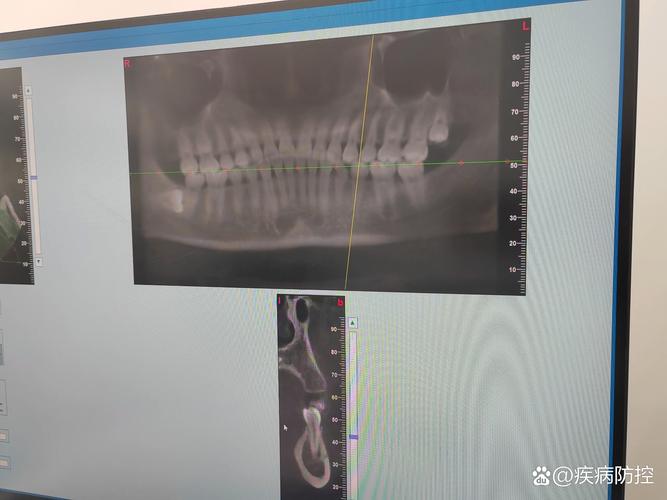

影像学表现

早期骨裂缝在根尖片上可能表现为牙根旁细线状低密度影,与牙根长轴平行;若裂缝较深或合并骨缺损,曲面断层片可见局部骨皮质连续性中断;CBCT(锥形束CT)可清晰显示裂缝的部位、走行、长度及骨缺损范围,是诊断的金标准。

影像学检查

不同影像学方法各有优势,可互补使用:

| 曲面断层片 | 可显示全口牙槽骨概况,对比双侧骨情况 | 分辨率低,细微裂缝易漏诊 | 评估下前牙区整体骨支持情况 |

| CBCT | 三维成像,高分辨率,清晰显示裂缝位置、范围、骨缺损程度 | 辐射较高,费用较高 | 确诊及制定治疗方案的关键依据 |